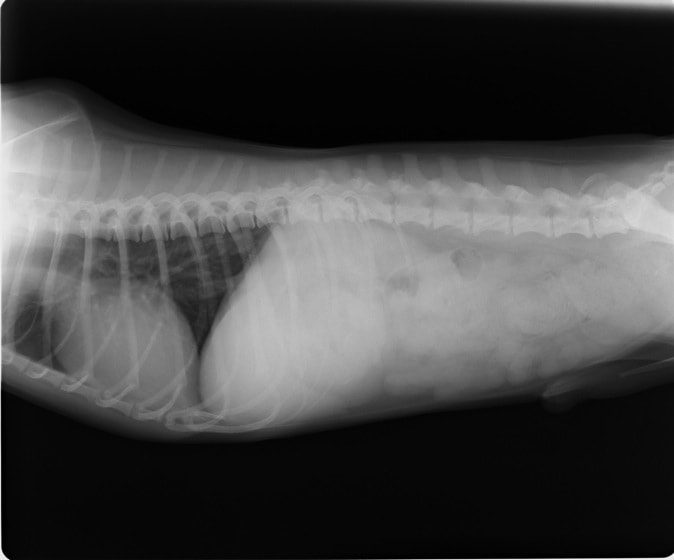

9歳 チワワ 4.8kg

主訴:2日前の夜に桃の種を飲み込んだとのこと。元気・食欲に問題はなく、嘔吐などの消化器症状もみられなかった。誤飲した当日に他院にて催吐処置を試みたが、吐き戻さなかったとのこと。

単純レントゲン検査:明らかな異常所見なし

消化管バリウム造影レントゲン検査:胃内にて異物の存在を疑う異常所見を認めた。

造影直後

内視鏡検査:内視鏡下にて、バスケット鉗子を用いて胃内異物を摘出。

異物内容:桃の種 (約4cm大 写真上)、とうもろこしの芯 (約2.5cm大 写真下)

本症例は、床に落としてしまった桃の種を誤飲していました。動物の体格に対して異物が非常に大きく、開腹手術となる可能性があった症例でした。また、桃の種と一緒に出てきたとうもろこしの芯は、日々のおやつとして与えていたものということでした。とうもろこしの芯は非常に硬く、小さく切って与えても消化されず、長期間胃内に残ってしまうことや腸閉塞の原因となる為、注意が必要です。